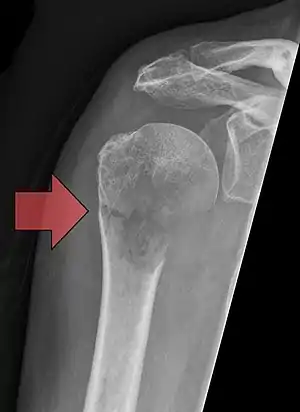

Pathological fracture of the humerus in a patient with metastasis of renal cell carcinoma

Pathological fractures present as a chalkstick fracture in long bones, and appear as a transverse fractures nearly 90 degrees to the long axis of the bone. In a pathological compression fracture of a spinal vertebra fractures will commonly appear to collapse the entire body of vertebra.